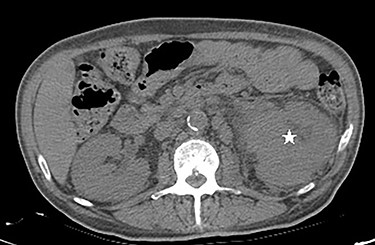

Computed tomography (CT) scan of the abdomen and pelvis showed poorly marginated soft tissue mass centered at the left renal pelvis (Fig. 3). Multiple prominent and enlarged retroperitoneal lymph nodes are noted. Additional CT chest imaging excluded other metastatic lesions.

Ureteroscopy was done and biopsies were taken from the renal pelvis. Biopsies of the mass showed a high-grade urothelial carcinoma invading the muscularis propria (pT2). Findings were consistent with metastatic UTUC.